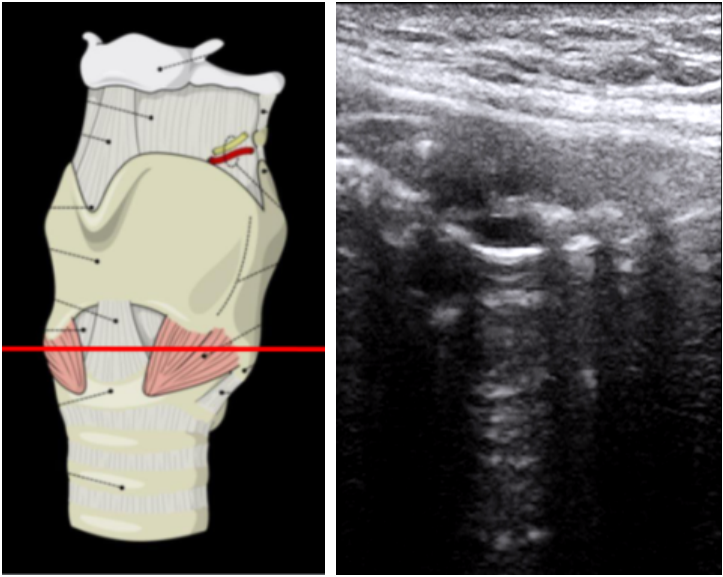

5. 环状软骨平面的扫查

在环甲膜扫查平面我们就发现了环状软骨和气管软骨。选择横向切面,可见一马蹄形低回声伴高回声气体黏膜的分界。图9右上绿色区域和右下绿色区域分别为横切面和纵切面的环状软骨。横切面环状软骨两侧的距离为环状软骨的直径。

图片

图9  环状软骨平面扫查

3. 甲状软骨平面的扫查

我们将高频线阵超声探头进一步下移,置于甲状软骨正前方,在没有甲状软骨钙化的个体,声带可以通过甲状软骨来呈现图6。对于钙化的个体,通过左右摇动探头30°左右来观察声带和杓状软骨。声带的声带肌表现为两三角形低回声结构,内侧为高回声的声带韧带。如果此时患者发声,可以发现两侧声带向中间运动的动态影像。

图6  甲状软骨平面的扫查和声带超声结构